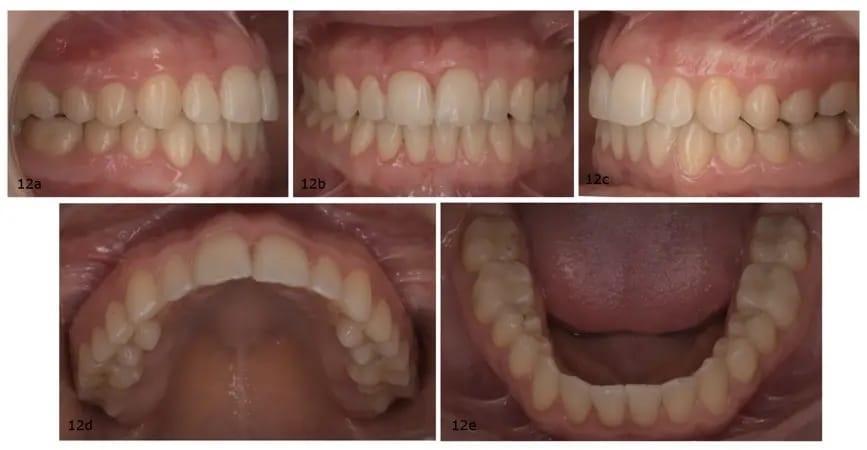

После 18 месяцев лечения, включая фазу восстановления и доработки, у пациентки наблюдались значительные улучшения в интраоральной области, в том числе более гармоничная линия улыбки, увеличенный вид резцов в состоянии покоя и заметное улучшение профиля лица благодаря эффективному автоматическому повороту нижней челюсти (фото 11). При интраоральном исследовании были получены следующие результаты: соотношение моляров и клыков I класса, правильное выравнивание обеих дуг, идеальный прикус, а также совпадение средних линий верхней и нижней челюсти (фото 12).

Фото 12a–e: Послеоперационные интраоральные фотографии.